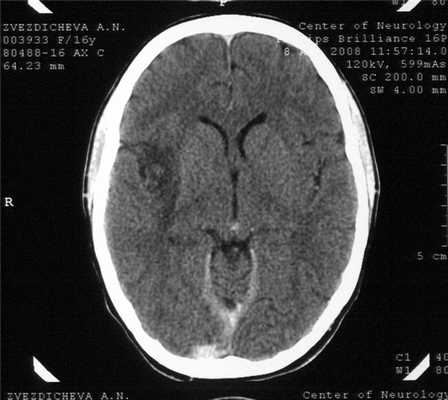

На 14-й день болезни (08.08.08) была проведена компьютерная томография (КТ) головного мозга. В правой височной области, островке и подлежащих отделах головного мозга выявлен очаг пониженной плотности неправильной формы, вероятно, воспалительного характера (рис. 1). Рисунок 1. КТ больной З. на 14-й день болезни. Очаг пониженной плотности в правой височной области и островке.

Результаты КТ свидетельствовали в пользу диагноза герпетического энцефалита, для которого характерны очаги пониженной плотности височной локализации [8, 14, 15]. В течение следующей недели у больной сохранялись высокая температура и спутанность сознания, повторялись эпизоды психических нарушений, галлюцинаций, в связи с чем были увеличены дозы противосудорожных и седативных препаратов. Периоды психического возбуждения сменялись эпизодами сонливости и заторможенности. Со стороны внутренних органов (дыхания и сердечной деятельности) отклонений не наблюдалось.